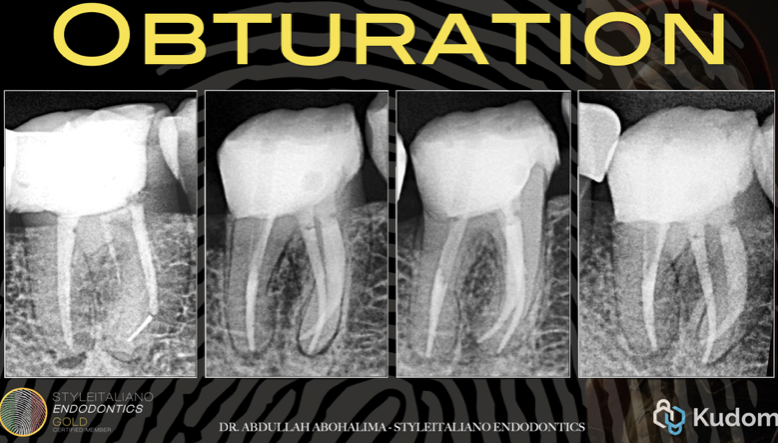

Moving on to obturation, it is important to pause and revisit a key principle discussed before starting the case the indications and limitations of file retrieval.

Comparison of pre-operative and post-operative radiographs demonstrates a conservative approach: both fractured files were successfully removed, and the canals were shaped while preserving tooth structure.

Despite performing coronal flaring and inner wall troughing, sufficient dentin thickness was preserved, owing to proper case selection from the outset.

The outlines of the gutta-percha and the root are clearly visible, confirming adequate remaining dentin and uniform canal shaping without over-troughing in any specific area.